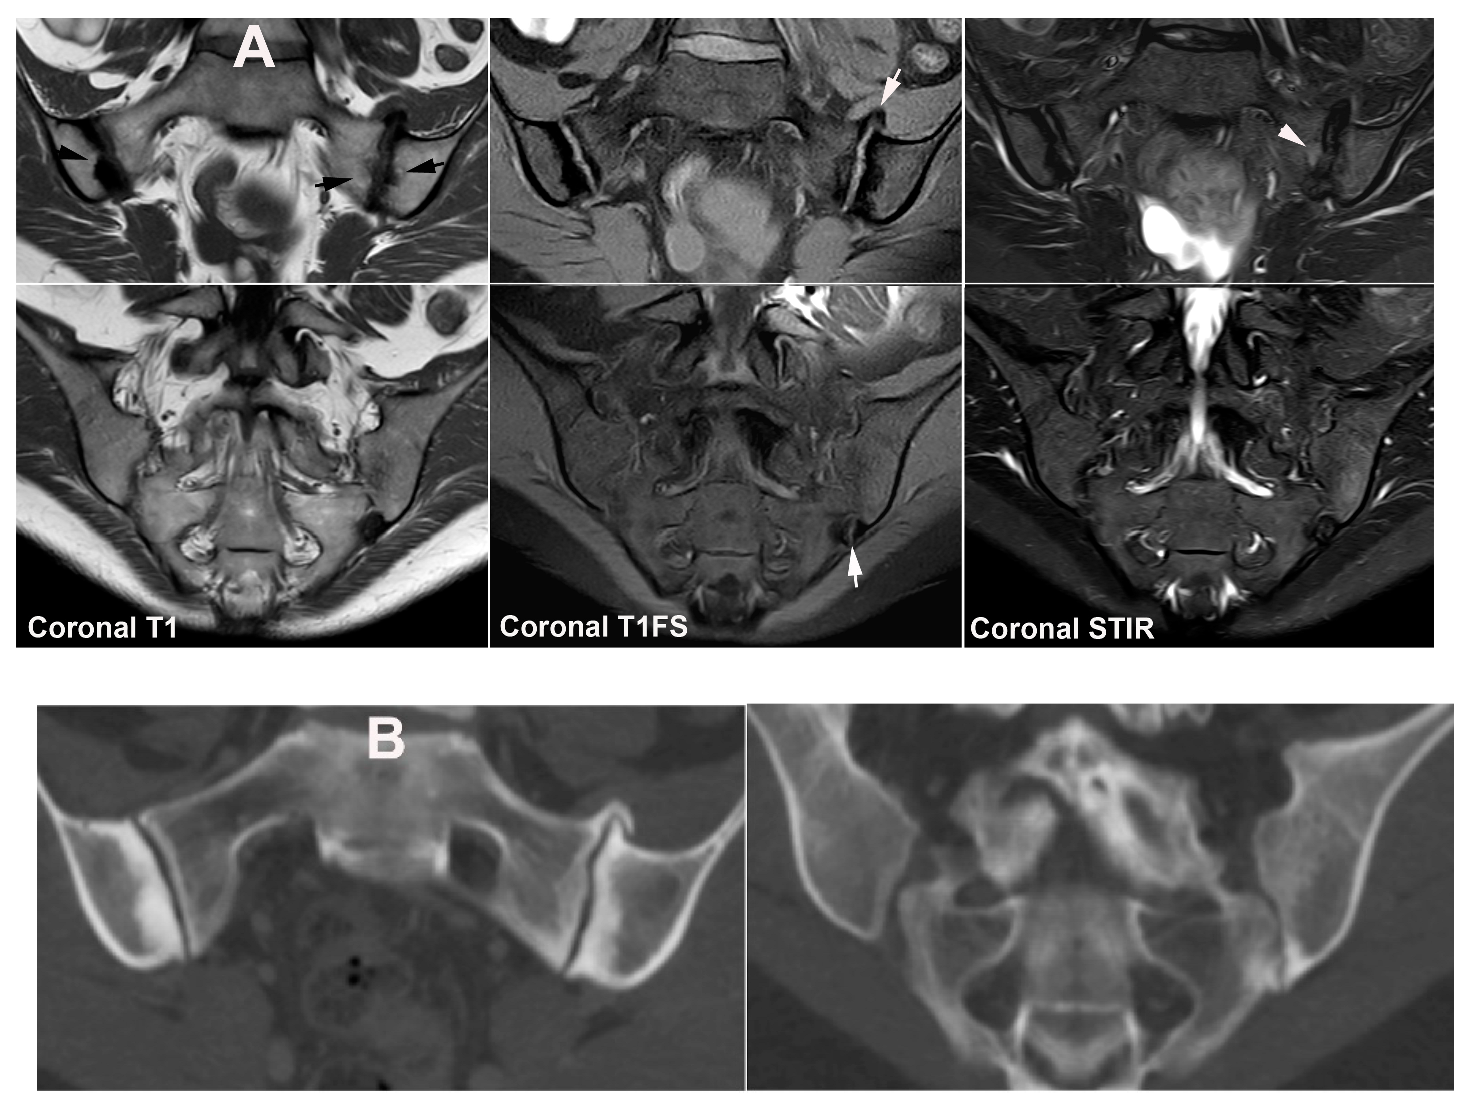

11.2. Chronic Non-Bacterial Osteitis (CNO)

12. Hyperparathyroidism and Other Disorders of Mineral Metabolism